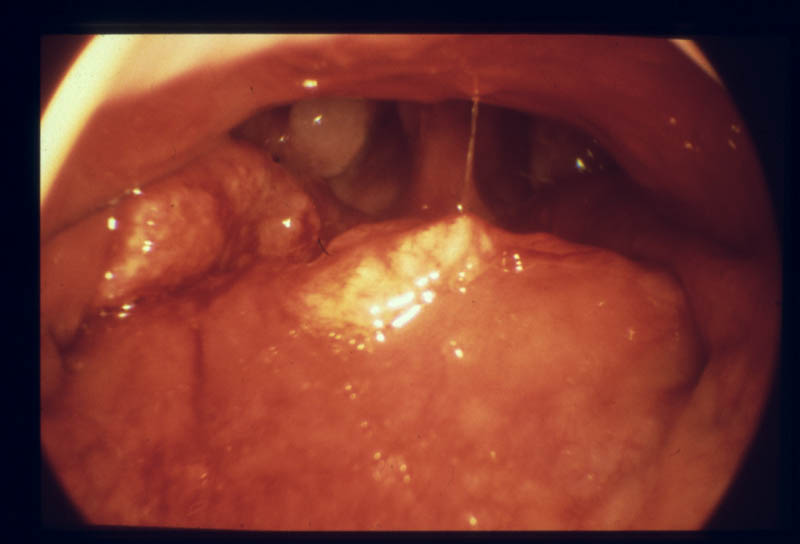

Adenoide (Rachenmandel) von der Nase aus mit dem Endoskop gesehen

Adenoide (Rachenmandel) vom Mund aus gesehen